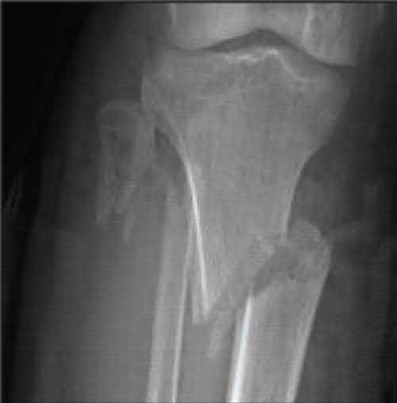

Figures A to C show radiographs of a 70 year-old male who fell on the ice 5 days ago. He could initially walk after the fall, but he is now unable to weight-bear on the leg due to pain. Physical examination shows diffuse ankle swelling, with no medial sided ankle tenderness. He is neurovascularly intact. The patient does not smoke and has no medical history. A gravity stress radiograph is demonstrated in Figure

D. After closed reduction, there is 2 mm of fracture displacement, no talar shift and the talocrural angle = 83 degrees. What is the most appropriate treatment?

Figure A demonstrates an AP radiograph of a Weber B fibula fracture with minimal medial clear space widening.

Figure B demonstrates a mortise radiograph of a Weber B fibula fracture with a congruent mortise.

Figure C demonstrates a lateral radiograph of a Weber B fibula fracture with a congruent mortise.

Figure D demonstrates a stress radiograph with minimal medial clear space widening.